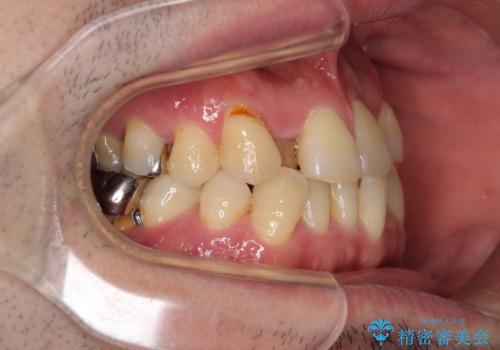

左右下顎の大臼歯は、ともに歯根が破折しており、抜歯が必要な状態でした。

放置したことで炎症による骨吸収が顕著であるため、骨造成を併用してインプラント埋入を行うこととしました。

咬み合わせは受け口傾向であり、上顎前歯の叢生が顕著であったことから、第1小臼歯抜歯による矯正治療も検討しましたが、下顎大臼歯を左右ともに抜歯するため、非抜歯による矯正治療を行うこととしました。